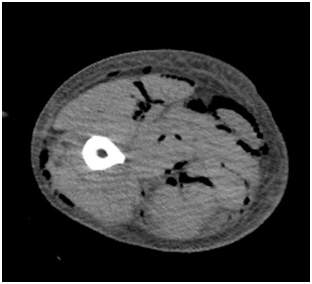

Figure 3A Axial CT of the thigh shows air densities within mucular compartments.

Abcess

Abscess may be simulated at imaging by necrotic tumors,myonecrosis due to severe trauma or extreme overuse, or ischemia (e.g., as can occur in patients with diabetes or sickle cell anemia).1

CT

Heterogenous fluid collection with thick irregular margins that enhance after the administration of intravenous contrast.

Inflammatory changes in the soft tissues adjacent to the abscess may lead to overestimation of its size.

CT is particularly useful for detecting gas present within the abscess cavity.

Both radiographs and CT can demonstrate retained foreign bodies that may be the cause of abscess

Adjacent soft tissue and skin inflammation are generally present (Figure 3B) (Figure 4).

Figure 4 Axial CT of the same patient reveals large abscess in calf muscles show air fluid level.